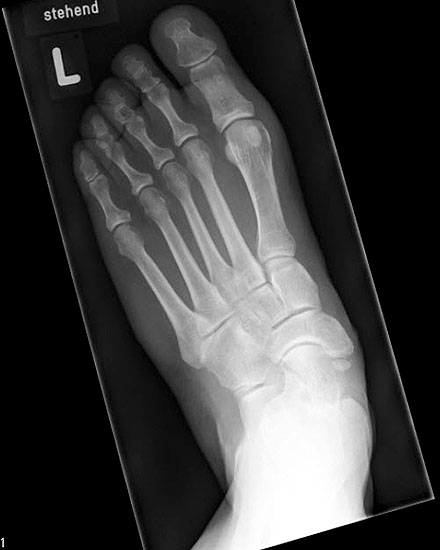

Stehende konventionelle Röntgenbilder eines Fußes mit Planovalgus Deformität Stadium II b dorsoplantar (dp) und seitlich. Auf der dp-Aufnahme zeigt sich die talo-calcaneare Divergenz, der gegenüber dem Kalkaneus nach anterior gleitende Talus und d

Abbildung 5

Stehende Aufnahmen des Fußes dorsoplantar (dp) und seitlich sowie des OSG anteroposterior (ap) sind die Grundlage der konventionellen Röntgendiagnostik (Abb. 5). Ergänzend werden gelegentlich die Rückfuβ-Alignement Aufnahme nach Saltzman 19 und Vergleichsaufnahmen der Gegenseite durchgeführt.

Der Talo-Metatarsale I Winkel bzw. die laterale talonaviculare Subluxation auf der stehenden dorsoplantaren Aufnahme des Fuβes dokumentieren das Ausmaβ des Vorfuβ abductus (Abb. 6 a,b). Ein dp Talo-Metatarsale I Winkel von > 10° (nach medial konvex) ist als pathologisch anzusehen. Mit der Bestimmung der talocalcanearen Divergenz (Abb. 6 c) erhält man ein Eindruck über das Ausmaβ des Rückfuβ valgus; eine leichte Divergenz bis ca. 12° gilt als physiologisch 20.

Auf der seitlichen, stehenden Aufnahme des Fußes wird ebenfalls der laterale Talo-Metatarsale I Winkel (Abb. 6 d) gemessen und so das kollabierte mediale Längsgewölbe dokumentiert. Auch hier gilt ein Talo-Metatarsale I Winkel von > 5° (nach plantar konvex) als pathologisch 21. Der Kollaps findet dabei meist im Talonaviculargelenk, seltener in der Naviculocuneiform-Gelenkreihe statt. Instabilität und Arthrose im 1. TMT sollten ausgeschlossen oder bei der Operationsplanung mit einbezogen werden. Weitere wichtige radiologische Messungen zur Beurteilung der Planovalgus-Statik und Progression der Deformität sind der laterale talo-calcaneare Winkel (Abb. 6 e) und der Abstand des Os cuneiforme-Unterrandes zum Untergrund (Abb. 6 f, Cuneiform height, 22. Eine anteriore Translation des Talus auf dem Kalkaneus findet man sowohl auf der ap, als auch auf der seitlichen Aufnahme des Fuβes mit Aufhebung der Cima-Linie.